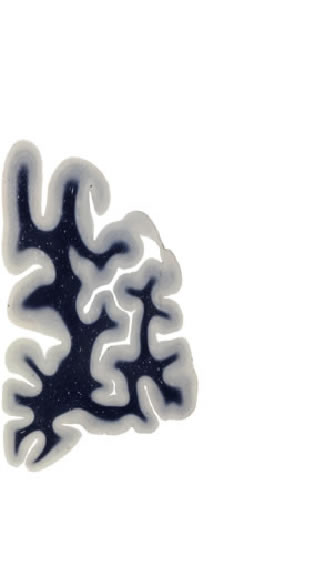

Hi-Resolution Sections · Cells (Nissl Staining) · Virtual Microscopy

Frontal sections (Nissl) from the Atlas Brain:

Slice ID:

r1-0500

Plate NR:

03

Position:

-47,9 mm